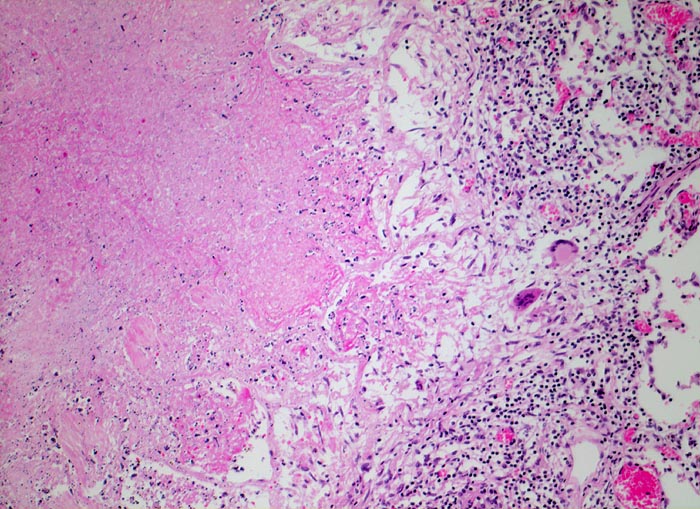

Das morphologische Bild ist äusserst variabel. Je nach Abwehrlage, Art und Geschwindigkeit der Ausbreitung entstehen unterschiedlich grosse, teils geschichtete Herde mit unterschiedlichem Grad an Epitheloidzellreaktion, zentraler Nekrose bzw. Vernarbung. Rein produktive Granulome ohne Nekrosen sind Zeichen guter Abwehrlage. Der Begriff Verkäsung bezieht sich auf den makroskopischen Aspekt von Nekrosen, der an Frischkäse erinnert. Exsudative nekrotisierende Granulome entstehen bevorzugt bei schlechter Abwehrlage. In späteren Stadien der Lungentuberkulose unterscheidet man produktive Phthisen mit azinös nodösen Gruppen von bronchogen entstandenen gering verkäsenden Streuherden (Präparat), zirrhotische Phthisen mit gering verkäsenden stark vernarbenden Herden und exsudative Phthisen bei schlechter Abwehrlage. Bei letzterer steht die Verkäsung im Vordergrund. Die bakterienreichen Herde entstehen teils hämatogen, teils bronchogen. Verkäsende Herde sind Ausgangspunkt für die Kavernenbildung. Kavernen stellen die wichtigste Quelle für die bronchogene Streuung dar.

• Tuberkulöse Herde ausgehend von vollständig oder partiell entzündlich zerstörten Bronchiolen in unmittelbarer Nachbarschaft von Arterien.

• Granulome mit zentraler käsiger Nekrose mit Kerntrümmern umgeben von einem Epitheloidzellwall und einem äusseren blauen Saum von Lymphozyten.

• Schlanke spindelige Epitheloidzellen und einzelne Riesenzellen vom Langhanstyp mit peripher hufeisenförmig angeordneten Kernen.